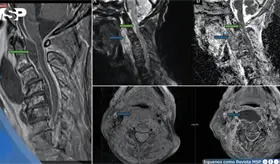

El intenso dolor torácico no fue una recaída ni metástasis, sino un daño óseo provocado por la reirradiación. Los huesos, debilitados por la radioterapia previa y la reirradiación, estaban perdiendo su capacidad de curarse adecuadamente.